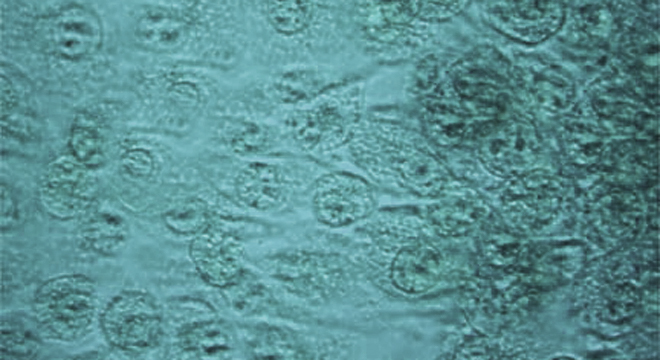

• Infektion mit spezifischen Bakterien (meist Chlamydien)